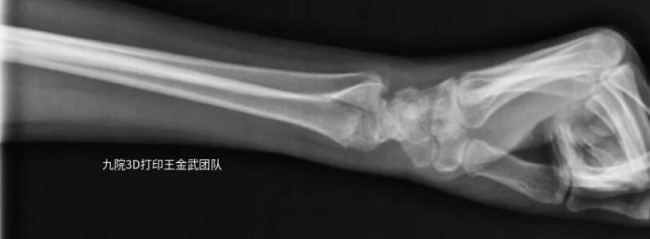

患者左臂桡骨远端骨折,骨折固定后佩戴3D打印固定支具辅助恢复情况良好。

▲佩戴3D打印固定支具后最终恢复情况